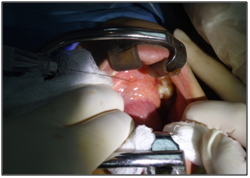

Preoperative studies were normal. Puncture is performed with fine needle whose cytology report concludes: Pleomorphic Adenoma. Later he prepares for surgery removal of submandibular gland with tumor intraorally (Figures 4) under general anesthesia with nasotracheal intubation.

Figure 4 Lidocaine with epinephrine (1: 100,000) is injected into the mucosa to achieve hemostasis.

The intra-oral route, requires nasotracheal intubation, after which lidocaine with epinephrine (1: 100,000) is injected into the mucosa to achieve hemostasis. After inserting a probe into the Wharton's duct meatus, an intraoral incision is made through the mucosa of the floor of the mouth, from the meatus behind the lingual side of the retromolar region. A careful dissection along the path through Wharton is duct shows its intimate relationship with the lingual nerve.